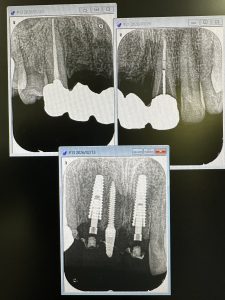

このような、軟組織のマネージメント移植やら仮歯、暫間インプラント、即時荷重料金も無し

患者さんが選択した47万コースには、CT撮影、診断からの全てインプラント料金に含まれているから、かなりお得で安い❗️🤪

40万コースは違うメーカーで埋入のみ、軟組織の処置は無し、仮歯は前歯領域隣接歯に固定ダミーだけ

1番上のコースはAGCガルバーノテレスコープ、ロングスパンのブリッジやらフルマウス症例時のみ、仮セメントは不要だが、技工代金が非常に高い😱